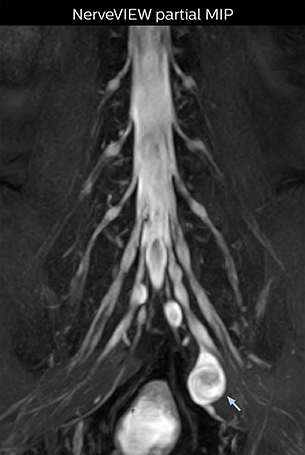

“In patients with lower extremity neurological symptoms, NerveVIEW helps us to determine the disease matching the patient’s symptoms by directly visualizing the nerves. We use the sequence mainly, when there is suspicion of intraforaminal stenosis, extraforaminal stenosis or lateral disc herniation, which is often based on routine T2- and T1-weighted images. Additionally, the excellent depiction of the course of nerves makes NerveVIEW a good navigator when applying treatment such as block therapy or surgery.”

“Before NerveVIEW, diagnosis by MRI alone was sometimes difficult, unless there was a strong suspicion based on clinical symptoms,” says Shoji Yabuki, MD, DMSc, Orthopedic surgeon at Fukushima Medical University School of Medicine. “This is why we routinely perform selective lumbosacral radiculography (nerve root block) and x-ray in such cases. However, radiculography can only depict nerves as far as the contrast agent reaches. When a nerve is distorted by compression, the contrast agent will not pass through this compressed area, preventing us from evaluating the full nerve compression.”

“In such case, we would then browse through axial T2-weighted MR images slice by slice and mentally reconstruct the actual situation based on both radiculography and MRI. Fortunately, NerveVIEW can now very well show nerve courses and presence of nerve compression or edema in one single image series.”

“We have often seen NerveVIEW directly depict details of the nerve compression that were not observed by radiculography. Therefore, we think that with NerveVIEW we can reduce the number of invasive examinations, especially for some patients with lumbar plexus symptoms.”

The key concept in MR neurography, Dr. Yabuki stresses, is the ability to directly visualize spinal nerves, versus inferring the presence of pathology indirectly. “Before NerveVIEW, we estimated compression of the nerve by looking for the presence or absence of fat signal on other MR images,” he says.

“For example, in sagittal images, when the presence of fat is observed in the intervertebral foramen, it suggests that there is a margin around the nerve. Similarly, the absence of fat indicates that the nerve is being compressed. So, we used to deduce nerve compression indirectly. With NerveVIEW, however, we can observe the condition of the nerves directly, regardless of the presence or absence of fat. We always prefer such direct observation of anatomy over having to make an inference about it.”

“NerveVIEW is really useful for those cases where a nerve disorder is strongly suspected based on the clinical examination but our regular MRI images do not show any findings. These atypical herniations and spinal canal stenosis, occurring in 5% to 15% of the total lumbar herniation/stenosis cases are our main target when using NerveVIEW,” says Dr. Yabuki.

“Although symptoms of typical disc herniation and atypical hernia are very similar, the actual site of herniation is different. It is therefore important to characterize the nerve’s condition both inside and outside of the intervertebral foramina.

“Conversely, if we see no abnormality in NerveVIEW, we can assume at least that there is no severe condition that requires surgery. Like this, it can help us avoid unnecessary surgery. NerveVIEW can have a tremendous impact in this way.”

Because the obtained NerveVIEW images often exhibit a high signal in the intervertebral discs, we use partial MIP images to eliminate such intervertebral disc high signals. MIP image generation is based on the  center of the coronal stack, and RAO (right anterior oblique) and LAO (left anterior oblique) images rotated in the range of 45 degrees are used for diagnosis.